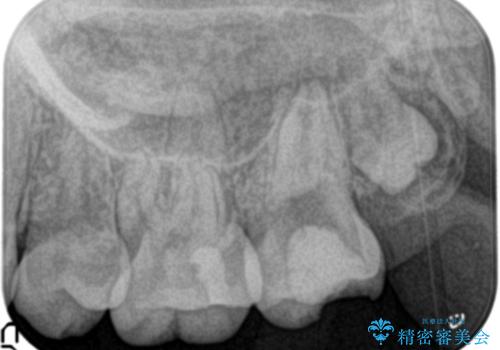

- 他院にて奥歯の治療をしても痛みが引かずに、ラバーダムの存在を知り、無菌的な治療を行える病院を探して当院を受診されました。

根管治療~フルジルコニアクラウンにて修復しております。

治療前には打診、圧痛がありましたが治療後には症状が消失し、3ヶ月後のレントゲンでも透過像の縮小を認めています。

治療介入時、根管内部にはカリエスや異物が存在する状態でしたが適切な処置を行うことで症状を改善することができました。